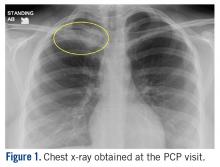

At the ED visit, she was noted to have an area of erythema and tenderness over the medial aspect of the right clavicle with increased bony prominence. A chest x-ray demonstrated medial clavicle enlargement with periosteal reaction and sclerosis (Figure 1) .